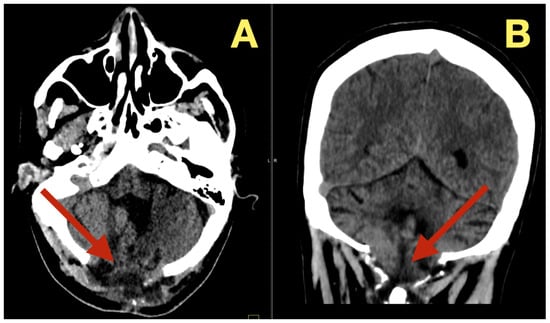

The preoperative MRI demonstrated a multilobulated mass within the fourth ventricle which was molded to the roof and cavity of the fourth ventricle. The mass arose from the inferior portion of the vermis and draped over the superior medullary velum and had smooth interfaces with the surrounding parenchyma which it displaced but did not invade. The mass was uniformly hypointense on T1 images; however, on T2/FLAIR images, the mass had hyperintensity with internal lobulation. The mass marginally compressed the uvula and nodulus and compressed the posterior surface of the pontine-medullary tegmentum. The foramen of Magendie was obliterated and both foramina of Luschka were narrowed resulting in an upstream flow void in the ventricles and a rim of periventricular interstitial edema. This created the hydrodynamic environment responsible for the patient’s symptoms. The worsening headache and vomiting in the morning, the papilledema, and nuchal rigidity resulted from the hydrodynamic environment. The avascular nature of the mass and the CSF conforming surface of the mass, as well as its central location, strongly suggested the possibility of an epidermoid cyst vs. a vascular neoplasm. The image-symptom correlation was excellent: the axial ataxia and titubation were due to compression of the fastigial nucleus and the vermian midline; the gaze-evoked nystagmus was due to disruption of the flocculonodular circuitry along the fourth ventricular roof; and the intracranial hypertension was due to obstruction of the caudal apertures. The morphology and epicenter of the mass were most consistent with a posterior fossa midline epidermoid tumor of Type 2 (fourth-ventricle epicenter) with a dominant relationship to the tela choroidea and cerebellomedullary fissure, anticipating a roof-centered growth pattern and possible focal adherence to the ventricular floor.

On the axial post contrast T1 plane (Figure 1A), the mass occupied the ventricular space like a mold, did not enhance, and was in the midline. The medial surface of the mass was in contact with the cerebellar vermis and the lateral surface of the mass slightly indented the tonsillar surfaces without penetrating into the parenchyma. On the mid sagittal T1 view (Figure 1B), the mass was in contact with the inferior vermis and caused an upward bowing of the superior medullary velum and flattening of the dorsal medulla and this explained the patient’s episodes of pressure-induced vomiting by mechanical stimulation of the area postrema. The coronal T1 reconstruction (Figure 1C) clearly demonstrated that the mass was in the midline and caused an equal compression of the two outlet recesses and was consistent with the absence of laterality in the patient’s deficits. On T2 (Figure 1D) and mid sagittal FLAIR (Figure 1E), the mass’ fluid-like appearance and internal lobulation were prominent; the surface of the mass was molded to the fourth ventricular CSF and not invading the fourth ventricular CSF, and this was a classic finding for this type of mass and accounted for the unusual severity of the fastigial/vermian hub being compressed and not destroyed.

Figure 1. Preoperative MRI of the posterior fossa. (A): Axial post-contrast T1: non-enhancing, lobulated mass centered in the fourth ventricle (arrow). (B): Mid-sagittal T1: inferior-vermis contact with upward bowing of the superior medullary velum and dorsal brainstem compression (arrow). (C): Coronal T1: strict midline localization with symmetric crowding of the ventricular outlets (arrow). (D): Axial T2: intrinsically high signal with molded margins against cerebellar tonsils (arrow). (E): Mid-sagittal FLAIR: high signal lesion with effacement of Magendie and narrowing of Luschka, concordant with obstructive hydrocephalus (arrow). Radioclinical correlation: vermian compression → truncal ataxia/titubation; flocculonodular disturbance → gaze-evoked nystagmus; outlet occlusion → intracranial hypertension.